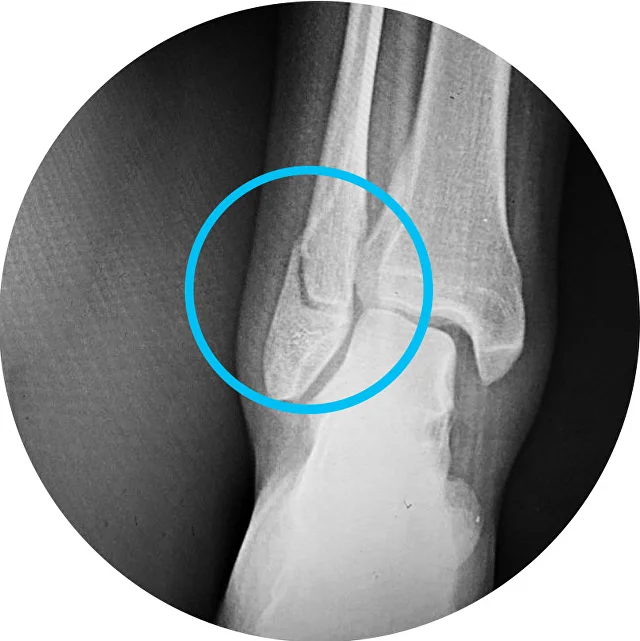

Переломы лодыжек включают как простые переломы наружной лодыжки, которые позволяют ходить с полной опорой на травмированную ногу, так и сложные двух- и трёх-лодыжечные переломы, с подвывихом и даже вывихом стопы, требующие хирургического лечения и . . .

кости выше синдесмоза • Перелом Фолькмана (Ирла): перелом латерального края «задней лодыжки» (заднего отдела большеберцовой кости): о 2 . КТ при переломе лодыжки: • Используется редко: о Позволяет подтвердить наличие перелома, плохо визуализирующегося . . .

Перелом лодыжек - это нарушение целостности лодыжек в результате травматического воздействия . Обычно возникает при подворачивании стопы кнаружи или кнутри . Проявляется болью, отеком, кровоподтеками, ограничением опоры и движений .

Перелом лодыжки — это один из наиболее частых видов травм, и он составляет до двух треть всех травм голени, и 21-23% по отношению ко всем травмам и повреждениям костей скелета . В зимнее время года, в условиях гололеда переломы лодыжек могут достигать размера . . .

Отдельно классифицируются: Переломы малоберцовой кости (наружной лодыжки) . Большеберцовой (внутренней лодыжки) . Особенность таких переломов в том, что иногда щиколотки как бы отрываются от костей голени: при подворачивании ноги, прочные связки . . .